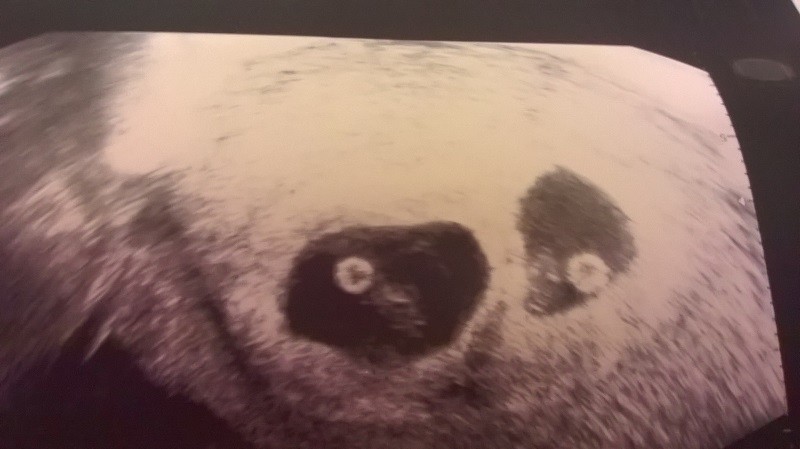

Dzieciaczki zdrowe, bo jak złapałam grypsko to poszłam do lekarza sprawdzić czy im nie zaszkodziło przypadkiem ... rosną, że hej. Troszkę młodsi są od obecnego terminu, wychodzi na 7t2i3dzień. Mają po 1.4cm i 1.8cm ..czy jakoś tak, bo mierzył od niechcenia ....wczoraj pierwszy raz dał mi posłuchać bicia ich serc ...strasznie się rozbeczałam, aż się lekarz na mnie patrzył jak na wariatkę ..ale siurek nigdy baby nie zrozumie

Proszę:

Zobacz załącznik 792791